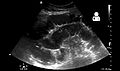

Radiological signs of bowel obstruction include bowel distension and the presence of multiple (more than six) gas-fluid levels on supine and erect abdominal radiographs.[medical citation needed] Ultrasounds may be as useful as CT scanning to make the diagnosis.[13]